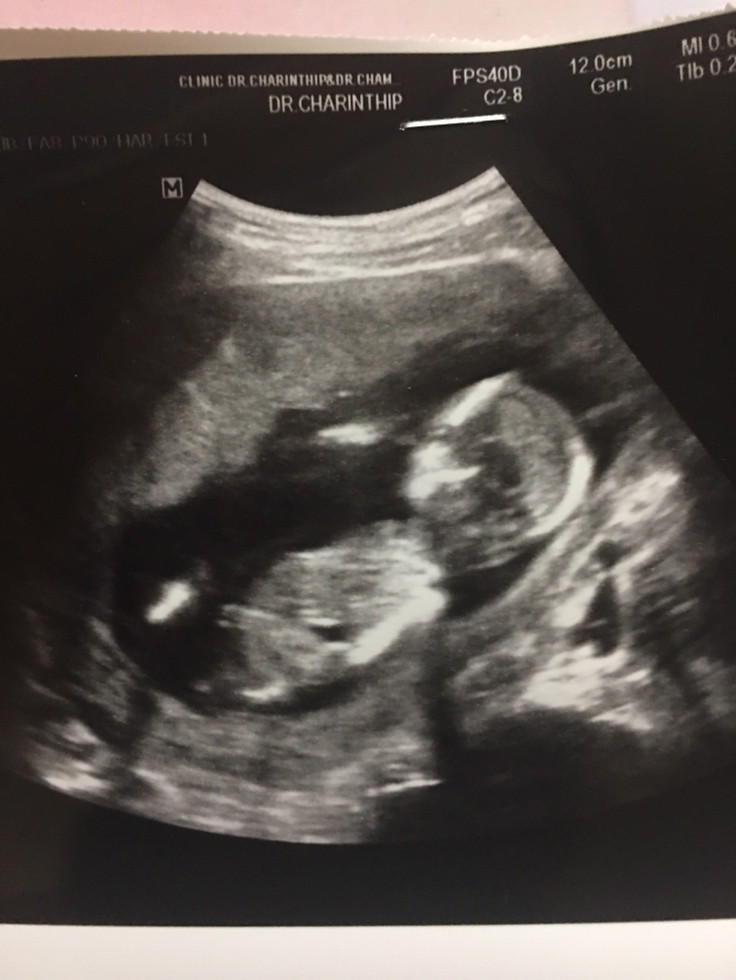

ขอดูภาพอัลตราซาวด์ของแม่ๆหน่อยค่ะ

ตั้งแต่ 8-13วีคค่ะ (ขอบคุณค่ะ)☺️☺️